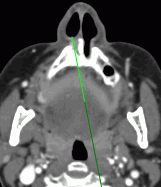

When building a marker line, the start and the end points are chosen on the selected sections. This allows for performance of measurements between the points placed on different sections. You can tell by the color of the marker line which part of it is in front of the current image. This part of the line will be brighter than the part placed behind the image (see Fig 5.23).

When building a polygonal marker line, the start and the end points, as well as the intermediate points, are chosen on the selected sections. This allows for performance of measurements between the points placed on different sections. You can tell by the color of the marker line which part of it is in front of the current image. This part of the line will be brighter than the part placed behind the image (see Fig 5.23).

You can determine how the marker line is located relative to the plane of the current image, judging by the color of the marker line. The line (or its part) located in front of the plane is brighter than the line (or its part) behind the plane. In Fig. 5.23, the bottom part of the line is located behind the image.